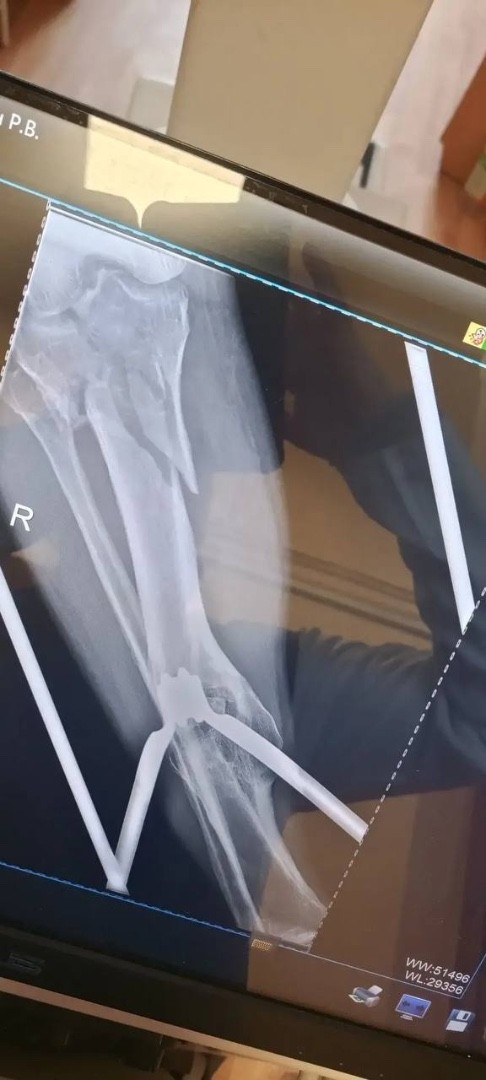

Травматологи горбольницы «Липецк - Мед» почти три часа буквально по кусочкам собирали голени пациента после аварии!

Пациент поступил после тяжелого ДТП 25 февраля с внутрисуставными переломами верхних зон обеих голеней.

Ситуация осложнялась хронической анемией на фоне кровопотери, что требовало особого подхода и скорости.

Заведующий отделением травматологии Дмитрий Соколов с ассистентом, врачом - травматологом Евгением Крюченковым провели одномоментное оперативное  вмешательство на двух конечностях с интраоперационной гемотрансфузией. То есть, оперировали одновременно обе ноги с минимальной кровопотерей.